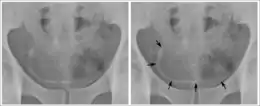

تصيب حصوات المثانة العديد من الحيوانات، بشكل شائع القطط والكلاب ولكن من الممكن حدوثها أيضًا في حيوانات أخرى بما في ذلك السلحفاة.